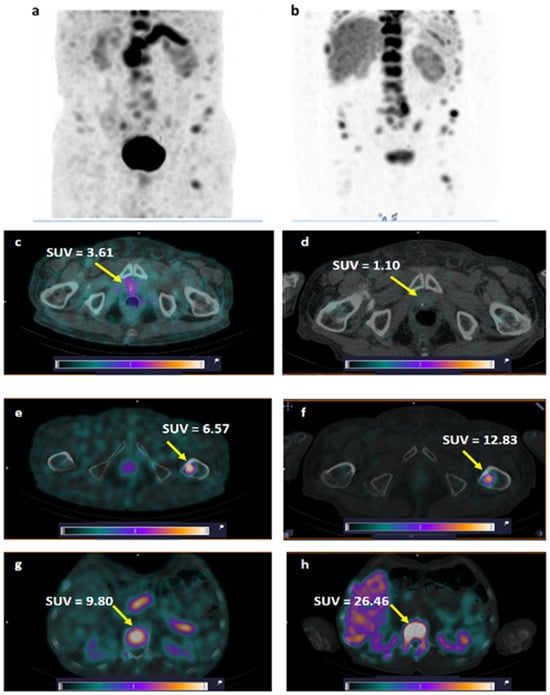

One patient (Patient 8, injected with a peptide mass of 80 µg) underwent SPECT visualization of PCa using the anti-PSMA targeting agent [99mTc]Tc-BQ0413 1 month before the current study (see Phase I study report [32], Patient 5). The comparison of GRPR SPECT and PSMA SPECT (Figure 8) revealed higher tumor uptake for [99mTc]Tc-DB8 in the primary lesion in the prostate gland. BM lesions were visualized with both agents; however, the contrast was higher for PSMA SPECT.

Figure 8. Comparison of visualization of GRPR expression using [99mTc]Tc-DB8 (a) and PSMA expression using [99mTc]Tc-BQ0413 (b) in primary tumor (c,d) and BM (eh) in Patient 8. A linear relative scale (normalized at the maximum activity in the image SUVmax from 0 to 5.0) is applied.

The comparison of GRPR and PSMA diagnostic images in Patient 8 (GS 9, PSA 800 ng/mL) demonstrated that the primary lesion in the prostate gland was clearly visualized only with the GPRP-targeting [99mTc]Tc-DB8 (SUVmax 3.61) but not with the PSMA-targeting [99mTc]Tc-BQ0413 (SUVmax 1.10). Conversely, LNMs and BMs had higher uptake in the case of [99mTc]Tc-BQ0413 (Figure 8). These results are in good agreement with other published clinical data when GRPR and PSMA diagnostic imaging peptides were head-to-head compared in large cohorts of PCa patients [8,9,58,59].